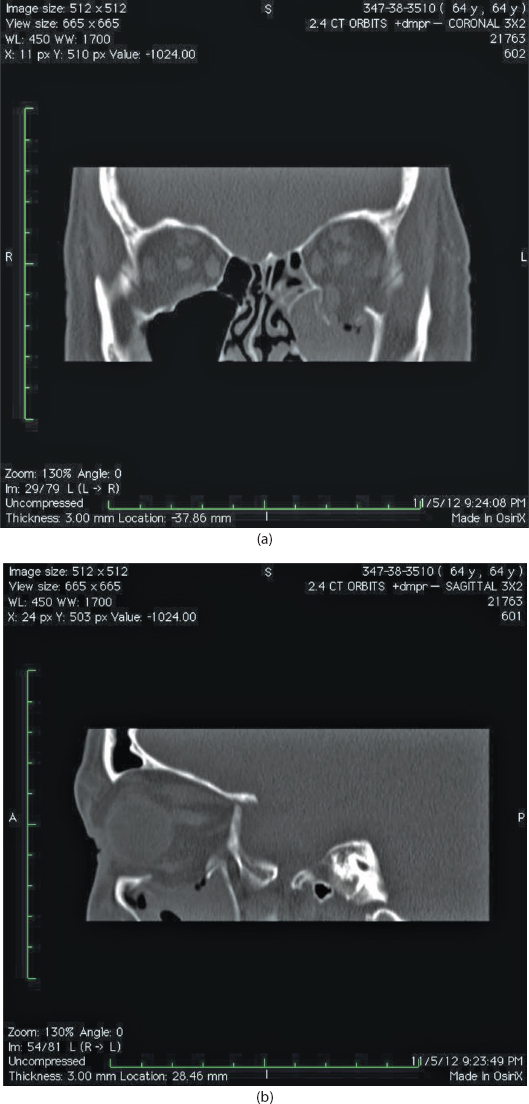

Isolated orbital floor fractures (blowouts) are often the result of impact injury to the globe resulting in a sudden increase in intraorbital hydraulic pressure. This kinetic energy is transmitted in an inferior and medial vector to the orbital floor (hydraulic theory) (Figure 13.1). Alternatively, the posterior transmission of a direct blow to the infraorbital rim causes buckling and resultant fracture of the orbital floor (buckling theory) (Figure 13.2). Fractures of the orbital floor can increase the volume of the orbit with resultant enophthalmos and hypoglobus. These can be highlighted on preoperative (Figure 13.3a–c) and postoperative (Figure 13.4a–c) computed tomographic (CT) scan imaging. In addition, the inferior rectus or periorbital soft tissue can become entrapped within the fracture line, resulting in restriction of extraocular eye movements. Table 13.1 indicates the special equipment used to surgically manage this injury.